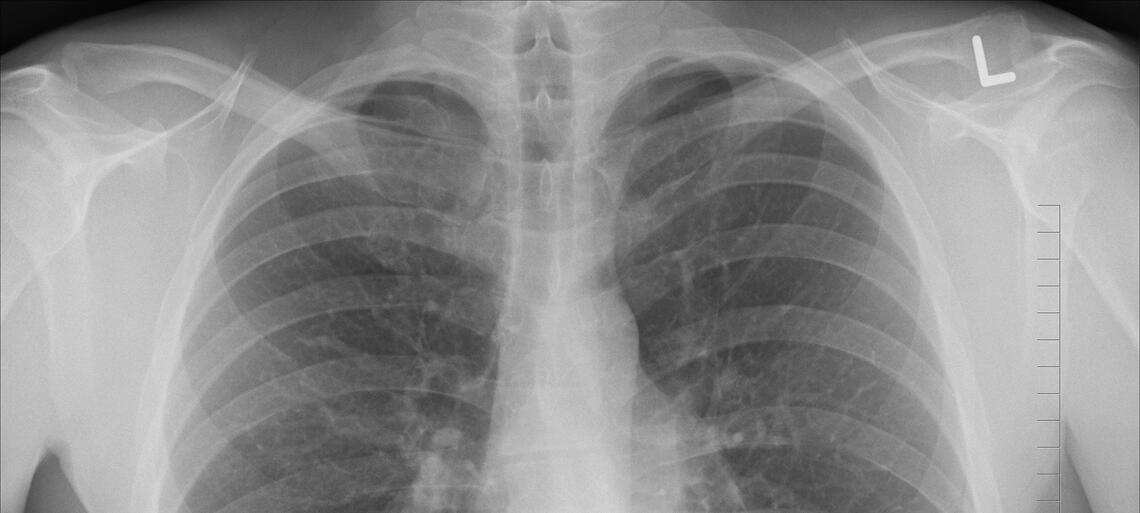

Scopo di questo lavoro è stato valutare, attraverso l’analisi di un registro internazionale multicentrico di pazienti ospedalizzati affetti da COVID-19, l’associazione tra la quantificazione tramite TAC toracica di tessuto adipodo epicardico, la gravità della polmonite e l’esito dell’infezione.

L’analisi clinica è stata eseguita su 109 pazienti con infezione da SARS-CoV-2 che sono stati sottoposti a TC toracica durante la degenza.

I parametri per la valutazione di EAT (volume e attenuazione), nonché l’estensione della polmonite, sono stati misurati utilizzando un software basato sull’intelligenza artificiale (“deep learning”).

I risultati hanno mostrato come EAT misurato su TAC toraciche sia associato in modo indipendente all’estensione della polmonite e al verificarsi di peggioramento clinico e/o decesso intraospedaliero in pazienti affetti da COVID-19.